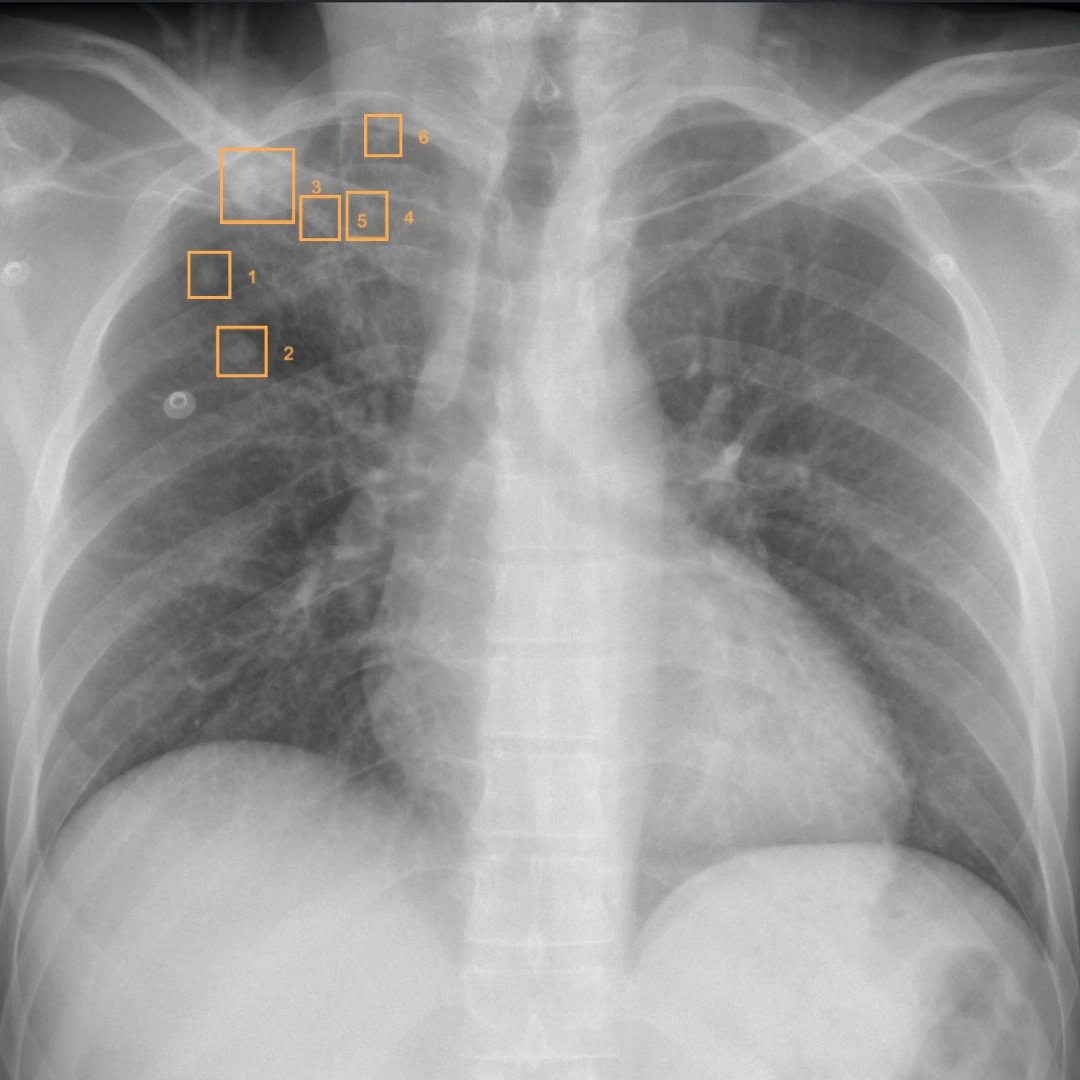

Routine chest X-ray workflow includes a wide range of overlapping patterns that require careful differentiation across heterogeneous cases.

CASE PRIORITIZATIONRAYSCAPE CXR AI brings computational clarity to everyday imaging, continuously analyzing chest X-rays to surface clinically meaningful patterns that might otherwise remain buried in visual complexity. By combining broad abnormality detection with advanced image enhancement, the system helps transform raw imaging data into structured, actionable insight.